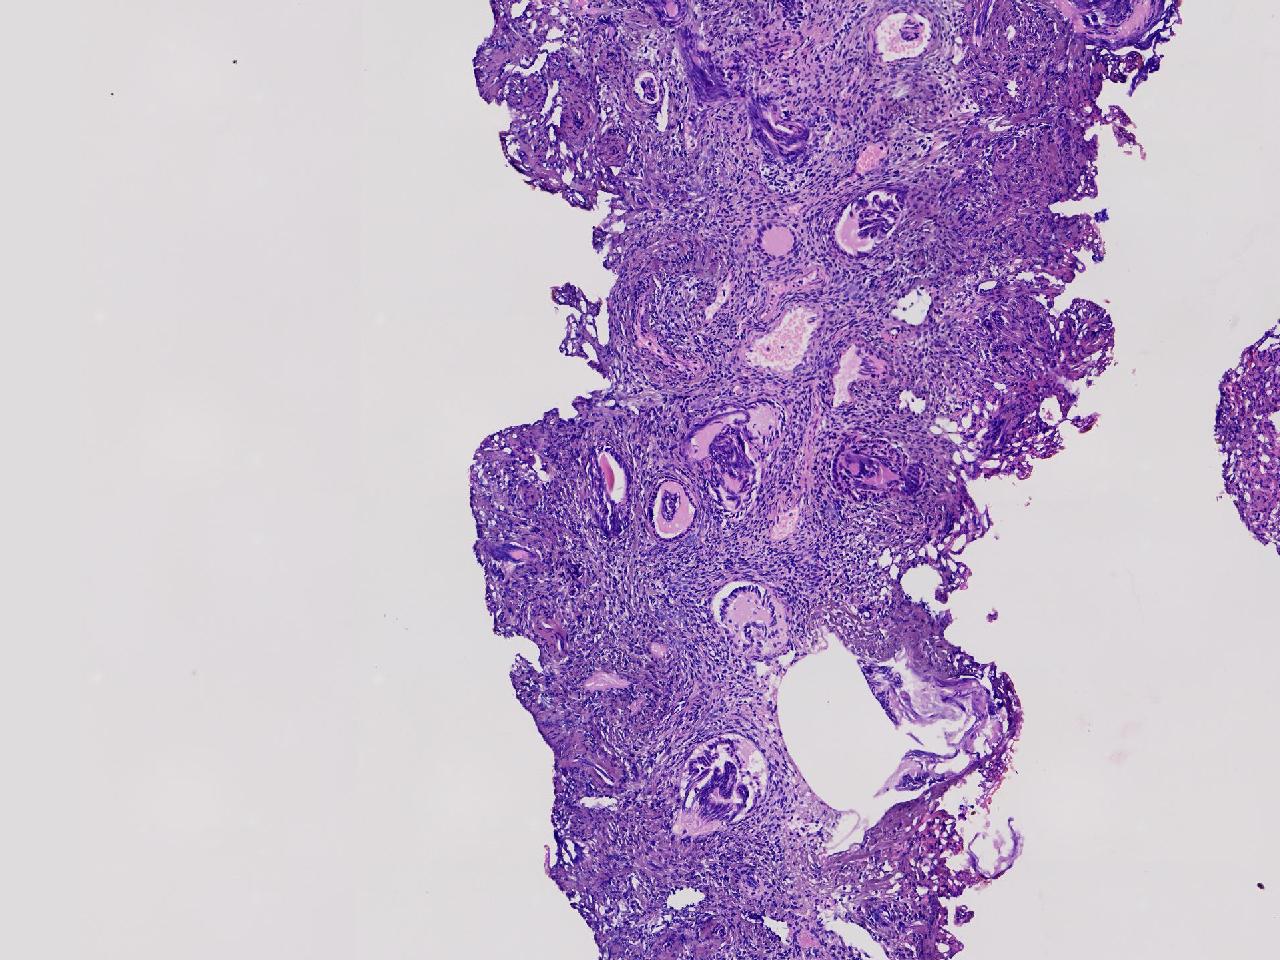

宫腔息肉?

性别

女

年龄

56岁

彩超示宫腔内见5x3ml的团状偏强回声结节,边界清。

灰粉色不整形软组织多块,0.5X0.3X0.3厘米。

首先考虑子宫内膜息肉,有些区域间质细胞较密,找找看有没有核分裂。

彩超提示强声团体积不小,待完整切除送检再综合诊断。